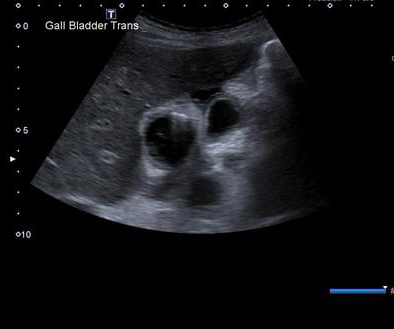

Cholecystite aigue

lithiasique : Images echographique de calcul

vesiculaire avec cone de hypoascoustique posterieure

. Distendue de la vesicule biliaire et epaissisement

de sa paroi . La contenue de la vesicule est

irreguliee . |